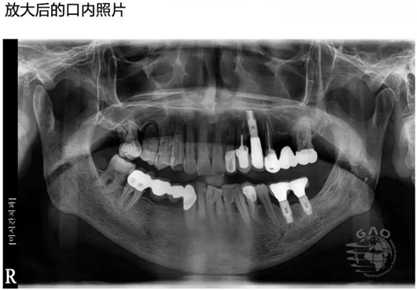

[臨床分享]使用取帽印模工具盒進(jìn)行下頜前牙區(qū)修復(fù) 科貿(mào)嘉友口腔收錄

- [臨床分享]使用取帽印模工具盒進(jìn)行下頜前牙區(qū)修復(fù) 科貿(mào)嘉友口腔收錄